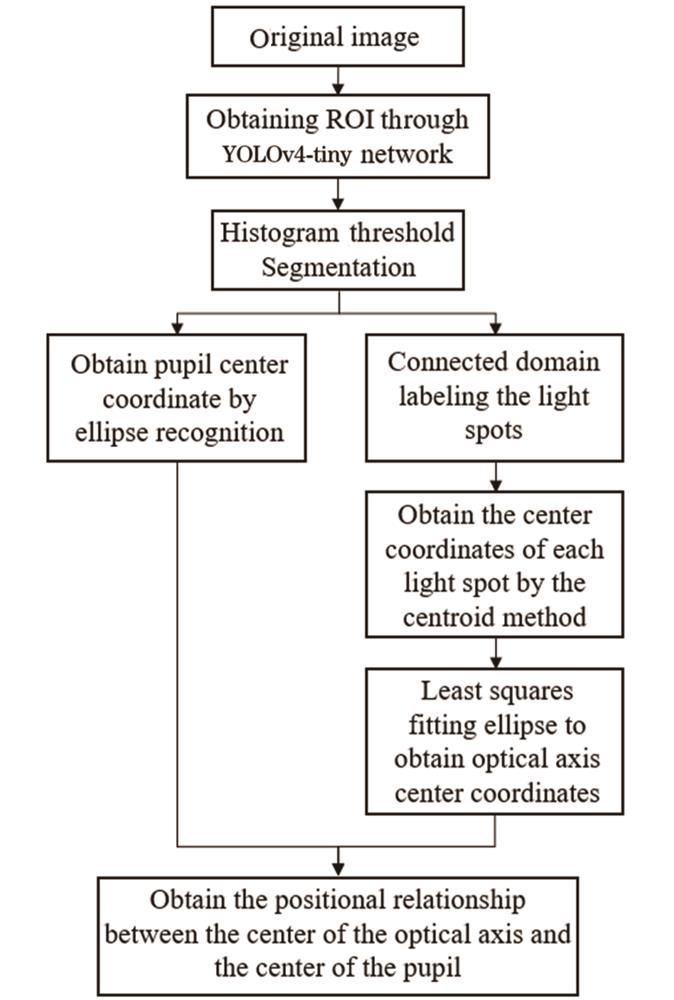

通过分析在正常光照下拍摄的人眼图像发现,睫毛和眼睑的遮挡、虹膜的泛灰色区域以及眼睑的大片明亮区域均可能对瞳孔中心的定位造成干扰,因此去除这些干扰项的影响是实现瞳孔中心定位的前提。本文提出一种融合卷积神经网络智能ROI窗口的瞳孔中心定位算法,该算法能有效提取瞳孔区域并进行中心定位,流程如

图 3. 瞳孔中心定位与对准算法的流程图

Fig. 3. Flowchart of pupil center positioning and alignment algorithm

4.1 感兴趣区域提取与二值化分割

人眼图像的灰度主要分为三部分:瞳孔及睫毛的低灰度部分、虹膜的中灰度部分,以及反射亮点和明亮区域的高灰度部分。但是各灰度分布之间并非以单独块状形式存在,这将对二值化分割以及后续的瞳孔椭圆识别造成干扰,影响算法的普适性。因此,本文采用YOLOv4-tiny算法[17]实现瞳孔区域的提取,该算法是YOLOv4目标检测算法的轻量化版本,骨干网络为CSPDarknet53-tiny,具有极高的检测速度,能够满足本系统的实时性要求。

经阈值T2分割后的图像中的8个白色小区域代表8个LED灯珠在角膜上反射的光点,这8个光点的中心即为测量光轴的中心。首先通过连通域标记的方法[19],将这8个小区域进行标记,然后利用质心法计算其质心坐标,最后对8个质心坐标进行最小二次椭圆拟合,并求取椭圆中心,该中心点即为测量光轴在图像上的坐标。本步骤处理后的结果如

在得到瞳孔中心和光轴的图像坐标后,计算两者之间的相互关系,再通过位移台X和Y方向的移动,使得瞳孔中心与光轴重合,实现瞳孔对准。瞳孔中心与光轴相对位置的示意图如